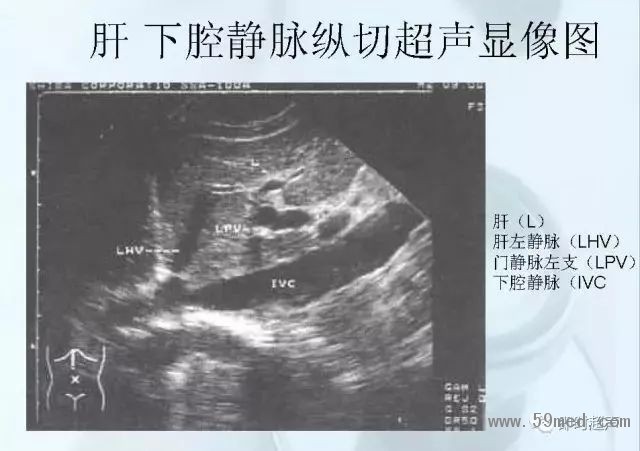

新聞中心 收藏!正常B超解剖圖譜,超實用!

![]() ![]() ![]() ![]() ![]() ![]() ![]() ![]() ![]() ![]() ![]() ![]() ![]() ![]() ![]() ![]() ![]() ![]() ![]() ![]() ![]() ![]() ![]() ![]() ![]() ![]() ![]() ![]() ![]() ![]() ![]() ![]() ![]() ![]() ![]() ![]() ![]() 【注:本文來源于即時超聲,版權(quán)歸原作者所有,如有侵權(quán) 請聯(lián)系 速刪】 =========================== 【閱精彩*悅分享】隨手點擊轉(zhuǎn)至朋友圈,與大家一起分享精彩資訊!當(dāng)然您也可以通過以下方式找到我,與您共同分享藍(lán)韻影像超聲的更多精彩!微信號:landultrasound 電話:+86-0755-66869896 24小時客服熱線:400-888-6452